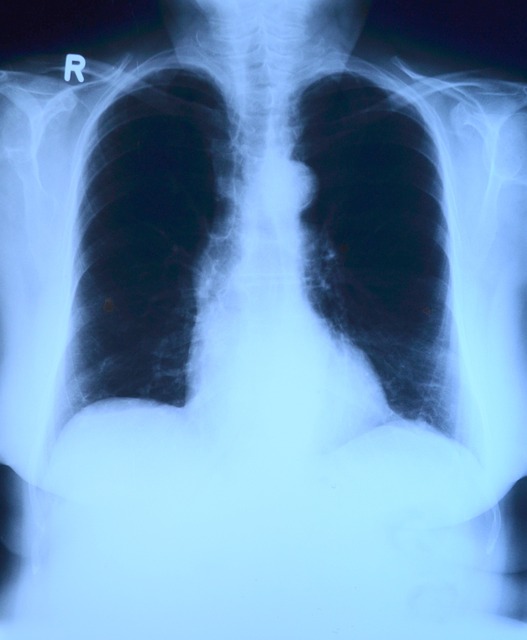

폐렴구균은 급성 중이염, 폐렴 및 균혈증, 수막염 등 침습성 감염을 일으키는 주요 원인균 중 하나입니다. 폐렴은 바이러스와 세균, 곰팡이 등이 폐에 침투해 발생하는 염증입니다. 폐렴의 증상은 감기와 비슷하지만 면역력이 약한 영아와 노인에게는 치명적일 수 있고 또한 폐렴구균에 의한 침습성 감염은 영아 및 65세 이상 고령자에게 발생 빈도가 높습니다. 그렇기 때문에 중년층 이상 노인들에게는 대상포진과 함께 꼭 예방접종을 해야할 질환 중 하나입니다. 또한 나이가 젊더라도 호흡기 질환을 앓고 있다면 접종을 권장합니다.